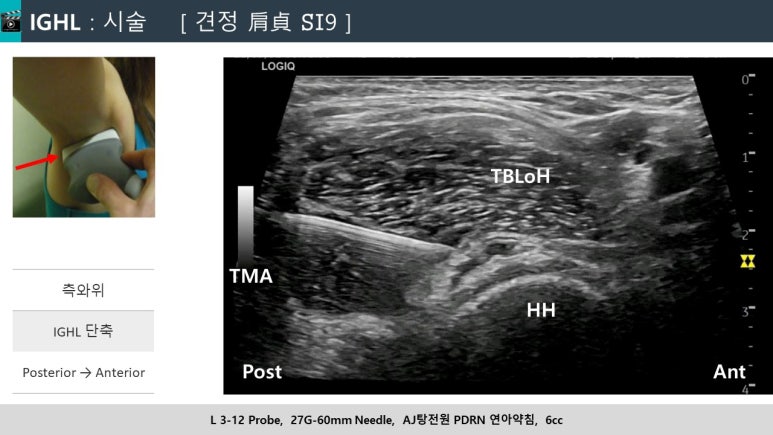

DOI: 10.7759/cureus.60157 1. 흉배신경 (TDN) 치료: 환자는 눕거나 엎드린 자세에서 진행됩니다. 광배근(LD), 대원근(TM), 견갑하근(SSC) 사이를 지나는 흉배동맥을 이정표(landmark) 삼아 신경 다발을 찾아냅니다. 이곳에 약침을 정밀하게 주입하여, 신경과 주변 유착된 조직 사이를 부드럽게 분리시키고요.  2. 액와신경 (AxN) 치료: 다음은 옆으로 누운 자세에서 액와신경을 찾습니다. 액와동맥을 이정표 삼아 상완골두(HH), 대원근(TM), 소원근(Tm), 상완삼두근 장두(LTB)로 형성된 곳을 지나는 액와신경 다발을 확인합니다. 역시 초음파로 실시간 확인하면서 신경과 주변 조직을 떼어놓습니다. 이러한 치료는 유착된 신경의 움직임과 기능을 개선하고, 신경 주변의 국소 혈액 순환을 증진시켜서 신경에서 오는 통증을 완화하는 데 효과적입니다. > 결과는? > > 관절와순 파열 관절염 어깨 통증 치료 흉배신경에 시술 직후, 앞서 양성이었던 CAT 검사가 정상이 되었고, 액와신경 시술 직후에는 HFT 검사 역시 호전되었습니다. *즉각적으로

2. 액와신경 (AxN) 치료: 다음은 옆으로 누운 자세에서 액와신경을 찾습니다. 액와동맥을 이정표 삼아 상완골두(HH), 대원근(TM), 소원근(Tm), 상완삼두근 장두(LTB)로 형성된 곳을 지나는 액와신경 다발을 확인합니다. 역시 초음파로 실시간 확인하면서 신경과 주변 조직을 떼어놓습니다. 이러한 치료는 유착된 신경의 움직임과 기능을 개선하고, 신경 주변의 국소 혈액 순환을 증진시켜서 신경에서 오는 통증을 완화하는 데 효과적입니다. > 결과는? > > 관절와순 파열 관절염 어깨 통증 치료 흉배신경에 시술 직후, 앞서 양성이었던 CAT 검사가 정상이 되었고, 액와신경 시술 직후에는 HFT 검사 역시 호전되었습니다. *즉각적으로

신경의 유착을 풀어관절의 기능과 움직임을 정상화시킴으로써** SLAP 병변으로 인해 발생했던 증상이 사라진 것입니다. > 초음파 약침 > > 어깨 통증 특효혈, 견정혈 한의원에서 시행하는 초음파 약침 치료의 핵심도 바로 이 정밀한 시술에 있습니다. 특히 이러한 문제의 특효혈은 수태양소장경의 견정혈[肩貞 SI19] 인데요.  흉배신경(TDN)과 액와신경(AxN) 과 같은 해부학적 구조를 직접 확인하고요. 신경의 유착을 해소하고 염증을 줄여주는 PDRN 연아약침을 정밀 주사합니다. 이러한 접근은 SLAP 병변 뿐만 아니라 어깨 회전근개 손상, 관절염, 오십견 등에도 다빈도 치료 포인트가 됩니다. * * * 어깨 통증, 특히 만성적인 SLAP 병변이 있다면 파열된 구조에만 집중할 것이 아니라, **현재 통증의 원인이 무엇인지?잘 가려내야 합니다.이 때,

흉배신경(TDN)과 액와신경(AxN) 과 같은 해부학적 구조를 직접 확인하고요. 신경의 유착을 해소하고 염증을 줄여주는 PDRN 연아약침을 정밀 주사합니다. 이러한 접근은 SLAP 병변 뿐만 아니라 어깨 회전근개 손상, 관절염, 오십견 등에도 다빈도 치료 포인트가 됩니다. * * * 어깨 통증, 특히 만성적인 SLAP 병변이 있다면 파열된 구조에만 집중할 것이 아니라, **현재 통증의 원인이 무엇인지?잘 가려내야 합니다.이 때,